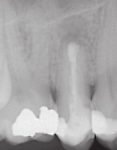

Die Wurzelspitzenresektion stellt bei therapieresistenten apikalen Prozessen nach wie vor eine gute Möglichkeit dar, Zähne im Munde unserer Patienten zu erhalten.

Bei nicht durchführbarer orthograder Aufbereitung (z. B. Stift, Kanalsklerose) oder bei apikal insuffizienter Abdichtung sollte idealerweise eine retrograde Kanalaufbereitung mit Ultraschallmikrospitzen und anschließender retrograder Kanalfüllung durchgeführt werden, um einen Zahnerhalt zu ermöglichen.

- Wurzelspitzenresektion

- Retrograde Kanalaufbereitung mit Ultraschallmikrospitzen

- Retrograder Kanalfüllung